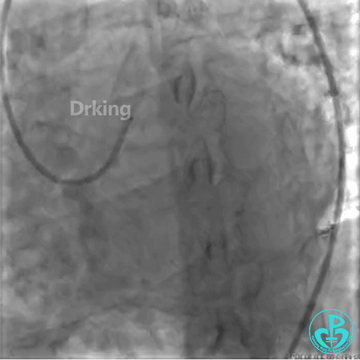

该患者于2019年03月28日在外院(县级市医院和地区级医学院附属大医院)两次冠脉造影术及PCI治疗均没成功,过程如下:

该患者近日转诊到江苏省人民医院,复查冠脉造影术,提示LCX近段扭曲严重(2处90度扭曲)的远段95%狭窄。当地医院市级及地区级医学院附属医院曾反复尝试,导丝均未能通过LCX近段扭曲处送至远段。